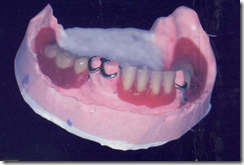

患者A先生

上顎 正面 下顎

患者B小姐

以上兩位患者口內狀況非常複雜,要制定一個好的治療計畫,

不只要考慮到患者的牙齒條件,

還要顧及患者意願、時間、金錢、評估可獲得的結果等等。

所以像這類型的Case 醫師通常在初步的溝通後會先做出一兩個不同的治療計畫,

再和患者解釋,了解患者接受程度。